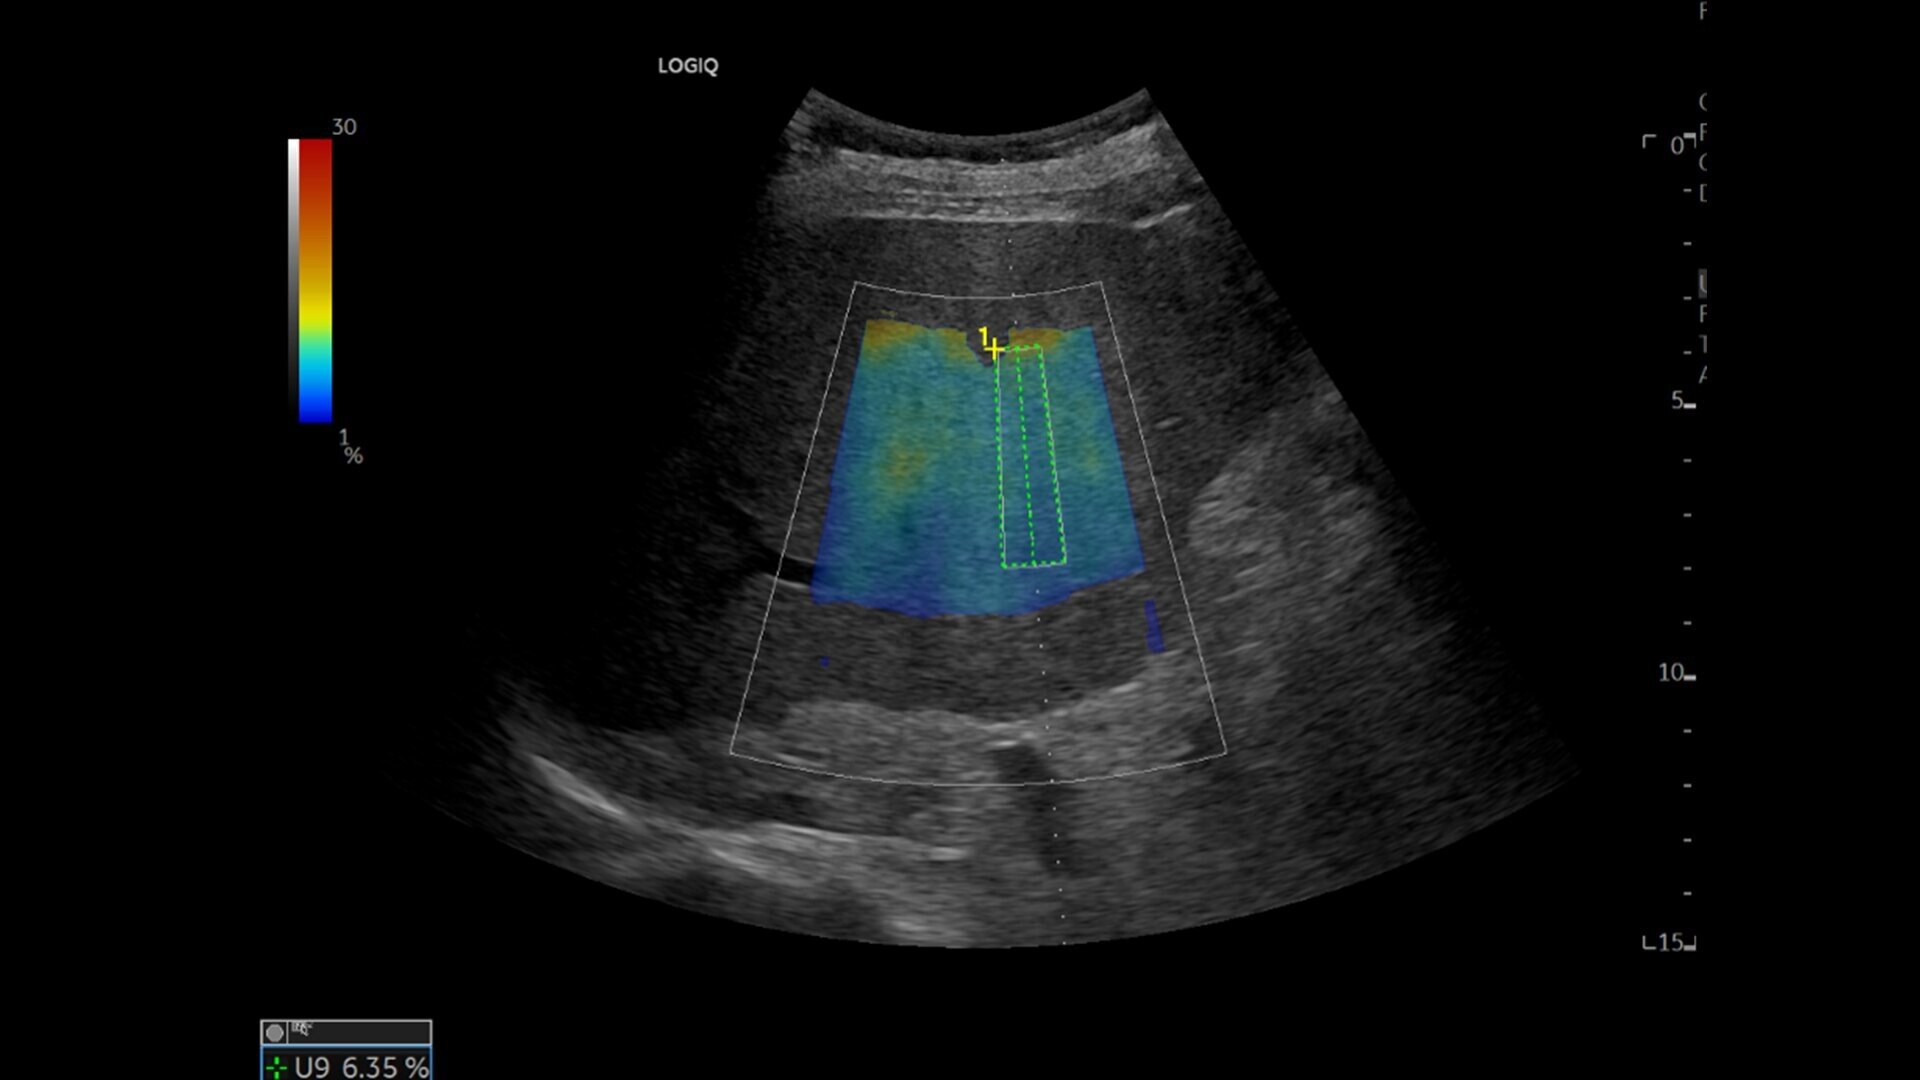

• Ultrasound-Guided Fat Fraction (UGFF) quantifies liver steatosis as a percentage, supporting detection and management - especially for patients with Metabolic Dysfunction-Associated Fatty Liver Disease (MAFLD)

• 2D shear wave elastography with quality map provides quantitative insight into tissue elasticity—helping you assess different structures with confidence